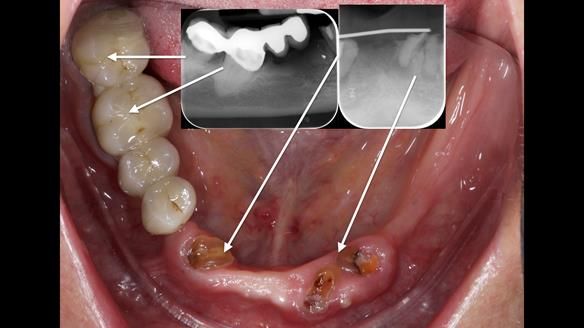

However, once Rowan and I reviewed the remaining metal crown on tooth 46, we realised it would make an ideal abutment for a gasket denture. By reshaping the lingual surface of the crown, we created an excellent gasket seal.

This approach worked far better than the proposed ring-clasp design - improving retention, comfort, and aesthetics while keeping the design clean and simple.